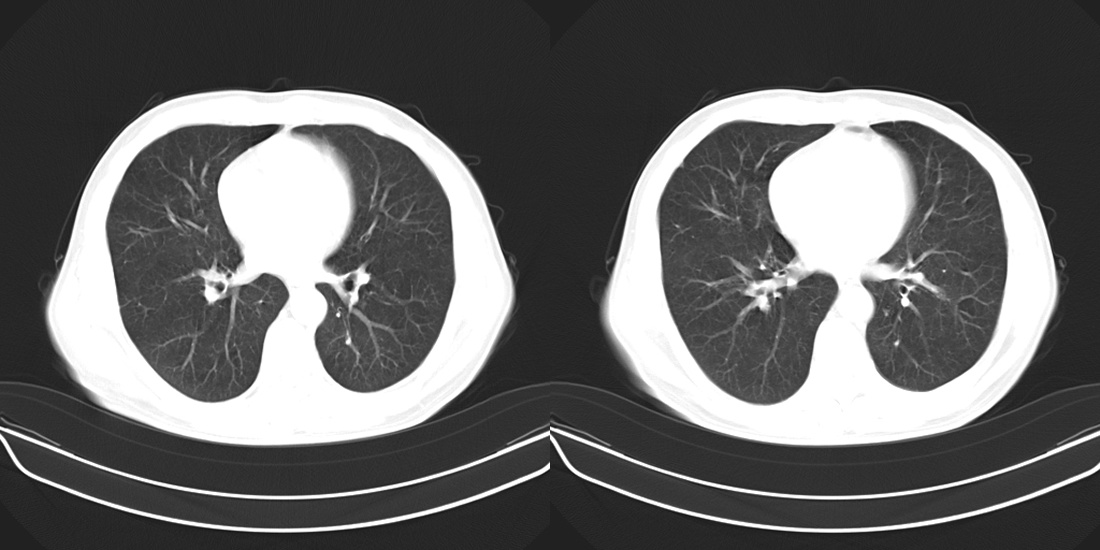

标题: CT10251:男性56岁,结核球? [打印本页]

标题: CT10251:男性56岁,结核球?

56岁男性,低热、消瘦,曾x线诊断肺结核。

两肺结核,左肺结核球。

双肺结核伴左上肺结核球形成

两肺多形性病变,支持肺结核.

两肺多形性病变,且在结核好发部位。支持肺结核.